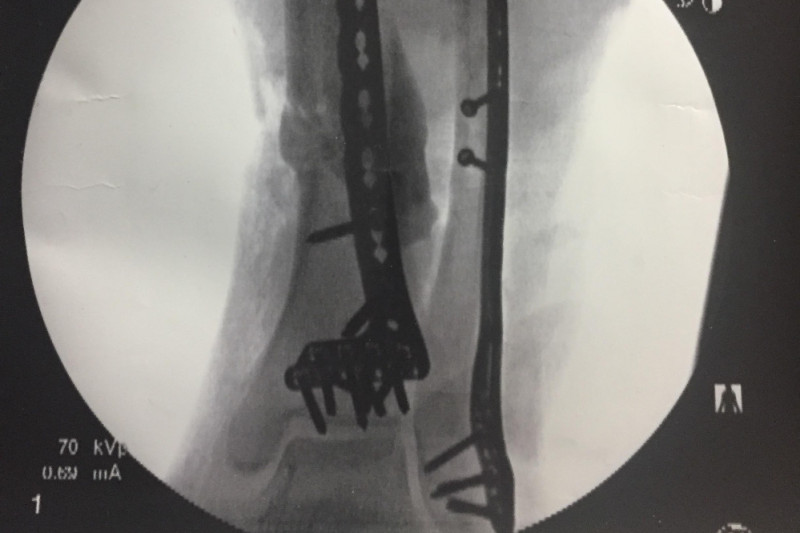

On Friday Sept 8th my brother Bear was on his way to meet some friends to get ready for for a weekend motorcycle trip to the Mackinac Bridge. On the way there a lady was coming down the wrong side of the road and Bear had to lay the bike down. She road up on the bike and then in a moment of panic after hitting him she backed up and dragged Bear and the bike for about two feet before the vehicle came back off the bike at which point the front end came down on Bears leg and blew his calf out. Luckily this happened next to a doctors office and the medical staff there rushed out and got a tourniquet on his leg and kept him from bleeding out until the EMTs arrived. He was taken to Holland Hospital via ambulance where they decided it was best to send him to Butterworth Hospital in Grand Rapids. He was in surgery for about four hours on Saturday the 9th where they discovered the damage was more severe than they thought. His calf muscle was split in two and not repairable via surgery and will have to heal on it's own, His Fibula had a clean break but the Tibia was smashed up pretty bad and there was a chunk of bone that came out and wasn't repairable so he will have to have a bone graft to replace it in 6-8 weeks. His ACL is intact and there was no nerve damage. Bears leg is being held together with some metal rods and screws right now and will be basically couch bound for the next few months and unable to work.